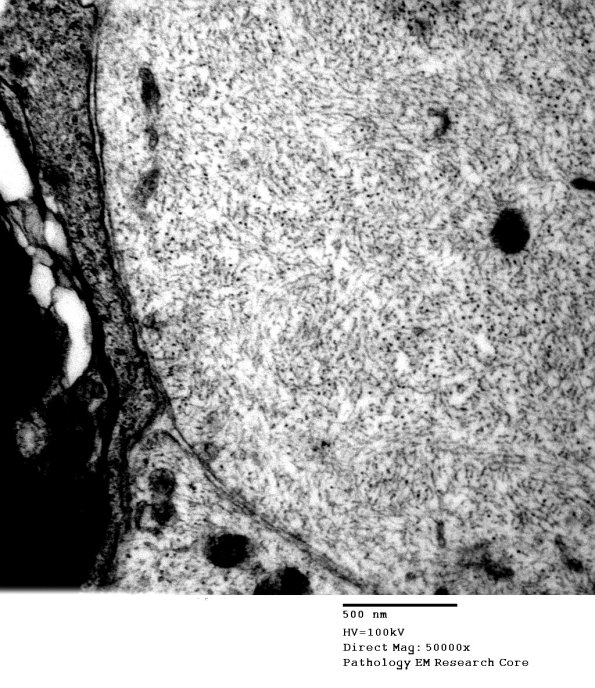

Higher magnification of image #1B1. (electron micrograph)